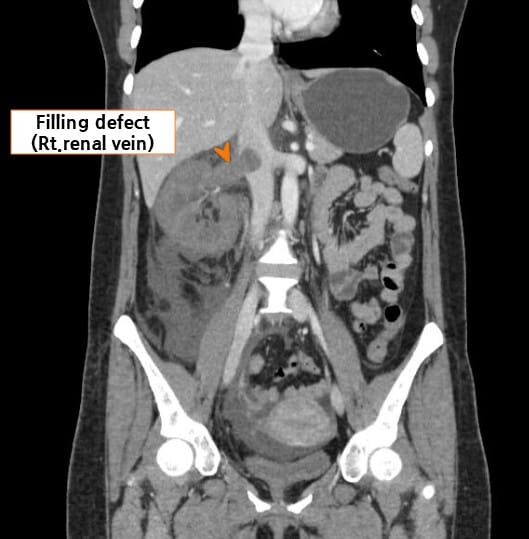

| CT 소견 |

| 🔴 신장 정맥에 filling defect 또는 혈류 차단 |

| 조영증강 CT 또는 MRI에서 신정맥 내 결손 음영이 보이며, 혈류가 차단된 모습이 나타날 수 있습니다. |

Abdrabou A, Renal vein thrombosis. Case study, Radiopaedia.org (Accessed on 23 Jul 2025) https://doi.org/10.53347/rID-51291